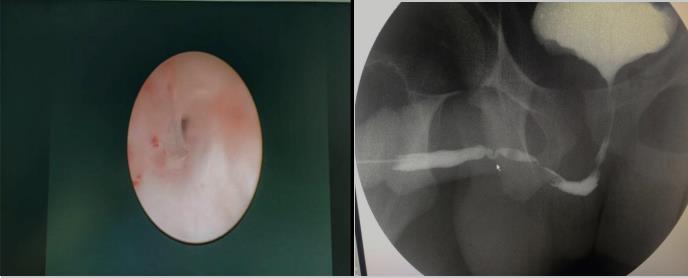

內(nèi)蒙古17歲的高三學(xué)生小馬,10年前做闌尾切除手術(shù),術(shù)后因留置尿管,逐步出現(xiàn)排尿不暢,從站立時(shí)排尿滴瀝,尿線細(xì),到站立時(shí)無(wú)法自解小便,后逐漸養(yǎng)成蹲位排尿習(xí)慣。正值高三關(guān)鍵階段的小馬,自覺(jué)排尿不暢較前明顯加重,已嚴(yán)重干擾平日學(xué)習(xí)和生活,痛苦不堪。父母帶小馬先后在內(nèi)蒙、上海等地就診,后經(jīng)親戚介紹,在我院泌尿外科入住。入院后強(qiáng)永春主任了解其病情后,通過(guò)尿流率檢測(cè)、尿道鏡檢查及尿道造影,明確患者前尿道兩段狹窄。與家屬充分溝通后,泌尿外科團(tuán)隊(duì)精心術(shù)前準(zhǔn)備,在全麻下行“頰粘膜尿道成形術(shù)”,術(shù)中證實(shí)前尿道兩處狹窄,狹窄段長(zhǎng)8㎝,取兩側(cè)頰粘膜各4×1cm,重建修復(fù)尿道狹窄。術(shù)后第2天,患者可進(jìn)少量流食,說(shuō)話正常,術(shù)后1周患者帶管好轉(zhuǎn)出院,出院3周患者來(lái)院復(fù)查,主管醫(yī)師張順給予拔除尿管后,小馬終于露出久違的笑容:“終于可以站著排尿了”。術(shù)后站立位查自然尿流率示:最大尿流率 19.2ml/s。手術(shù)效果滿意。

強(qiáng)永春副主任介紹說(shuō):尿道狹窄最常見的癥狀是尿流減少和膀胱不完全排空,也可以表現(xiàn)排尿困難、尿路感染、附睪炎、殘余尿量多。該患者考慮為尿路感染所致。尿道狹窄以往采用尿道擴(kuò)張、內(nèi)鏡切開及尿道成形術(shù)治療,但長(zhǎng)段的狹窄手術(shù)后效果并不滿意,現(xiàn)在有了粘膜組織移植,組織移植常選擇口腔粘膜(頰粘膜、舌粘膜和唇粘膜),手術(shù)效果好,但手術(shù)要求高,難度大。